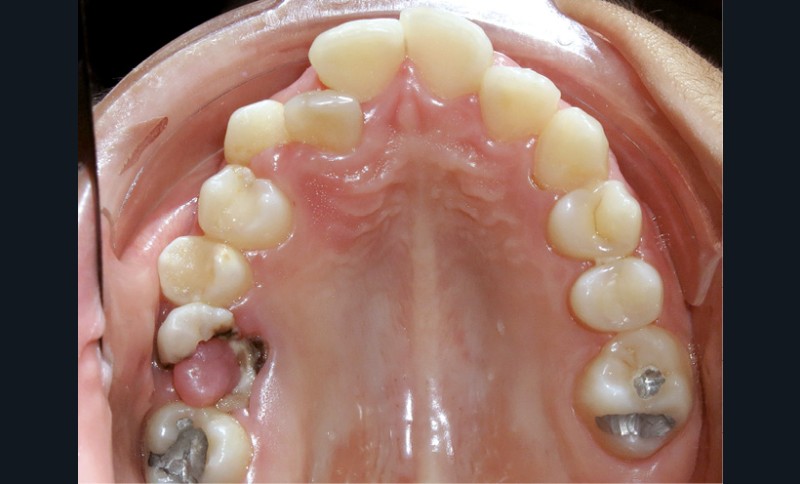

Le niveau d’hygiène est alarmant, car le rituel du brossage des dents n’est pas instauré dans la famille. Des caries se sont développées sur les dents temporaires et en ont imposé l’extraction. Les molaires permanentes ont dérivé mésialement, réduisant l’espace disponible sur l’arcade.

En denture adulte, la DDM est majeure avec un déficit de place estimé de 13 mm à la mandibule. Les lésions carieuses ont aussi touché les premières molaires permanentes maxillaires. La 26 a été avulsée et la 27 a pris sa place. Côté controlatéral, la 16 est fortement délabrée, rendant impossible sa conservation. Les molaires ayant plus mésialé à l’arcade mandibulaire, les rapports occlusaux sont de classe III. Les incisives sont versées vers l’avant, mais nous pouvons considérer qu‘il s’agit d’une biproalvéolie ethnique. Du point de vue squelettique, le patient présente une classe II squelettique par rétromandibulie sur un schéma facial hyperdivergent (fig. 1a-j).